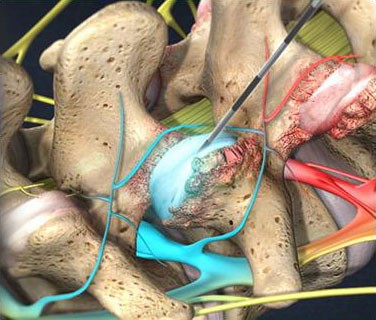

- Caudal Steroid Injection

- Facet Joint Injections

- Joint Steroid Injection

- Discography

- Lumbar Epidural Steroid Injection